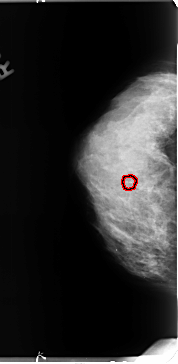

B_3127_1.RIGHT_MLO

RIGHT_MLO LINES 4664 PIXELS_PER_LINE 2456 BITS_PER_PIXEL 12 RESOLUTION 50 OVERLAY

FILE: B_3127_1.RIGHT_MLO.OVERLAY

TOTAL_ABNORMALITIES 1

ABNORMALITY 1

LESION_TYPE CALCIFICATION TYPE PLEOMORPHIC DISTRIBUTION CLUSTERED

ASSESSMENT 4

SUBTLETY 3

PATHOLOGY BENIGN

TOTAL_OUTLINES 1

BOUNDARY